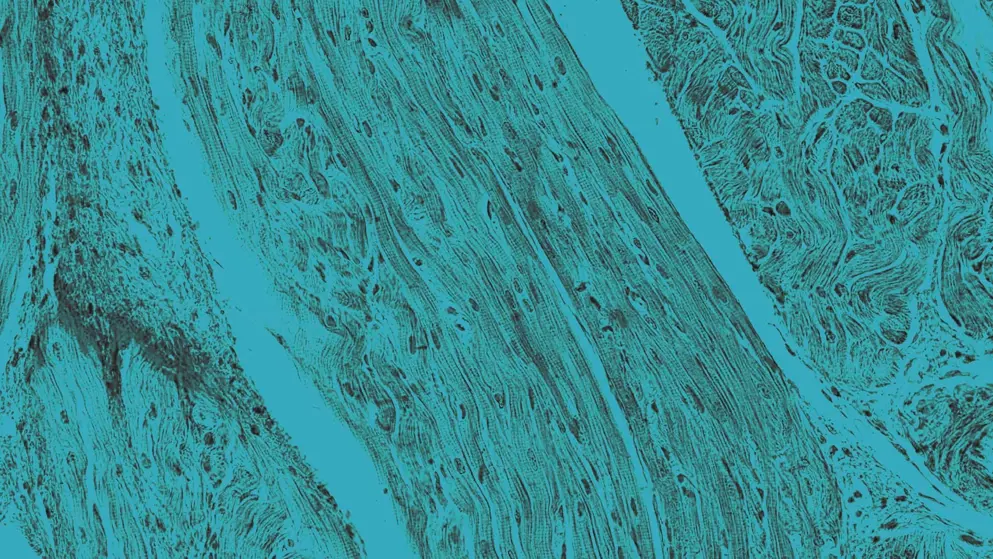

Arrhythmia refers to an irregular heartbeat caused by abnormal electrical impulses in the heart, leading to tachycardia, bradycardia, or erratic rhythms. Symptoms may include palpitations, dizziness, and fatigue. In some cases, arrhythmias can result in severe complications, such as stroke, blood clotting, heart failure, and sudden cardiac death. Common types include atrial fibrillation, atrial flutter, supraventricular tachycardia, ventricular fibrillation, and ventricular tachycardia.

Arrhythmias are often triggered by disruptions in the heart’s electrical conduction system. These may stem from structural heart disease, electrolyte imbalances, or autonomic nervous system instability. Common triggers include myocardial infarction, cardiomyopathy, thyroid disorders, stimulant use (e.g., caffeine, alcohol, certain drugs), and some medications. Sleep apnea and inherited channelopathies, such as long QT syndrome, are also recognized contributors.